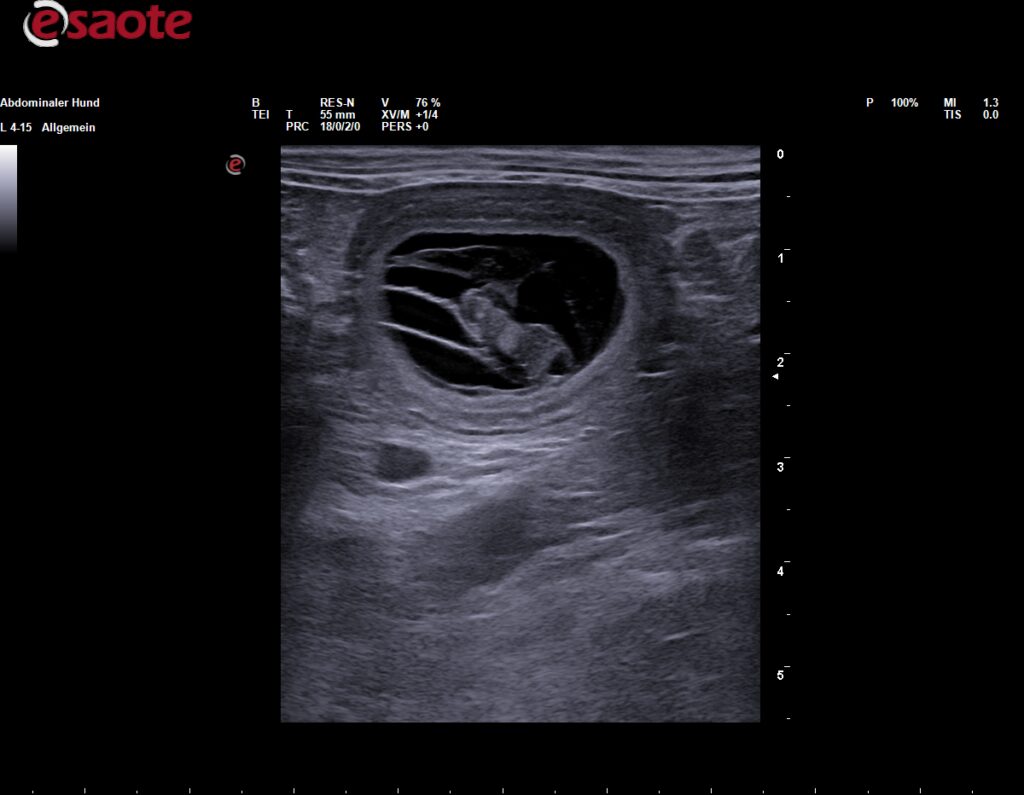

Am 03.09.2025 hat der Ultraschall es bestätigt, Baya ist trächtig! Es wurden mindestens 4 Welpen gesehen, es bleibt spannend. In der ersten Oktoberwoche kommt unser G-Wurf zur Welt.